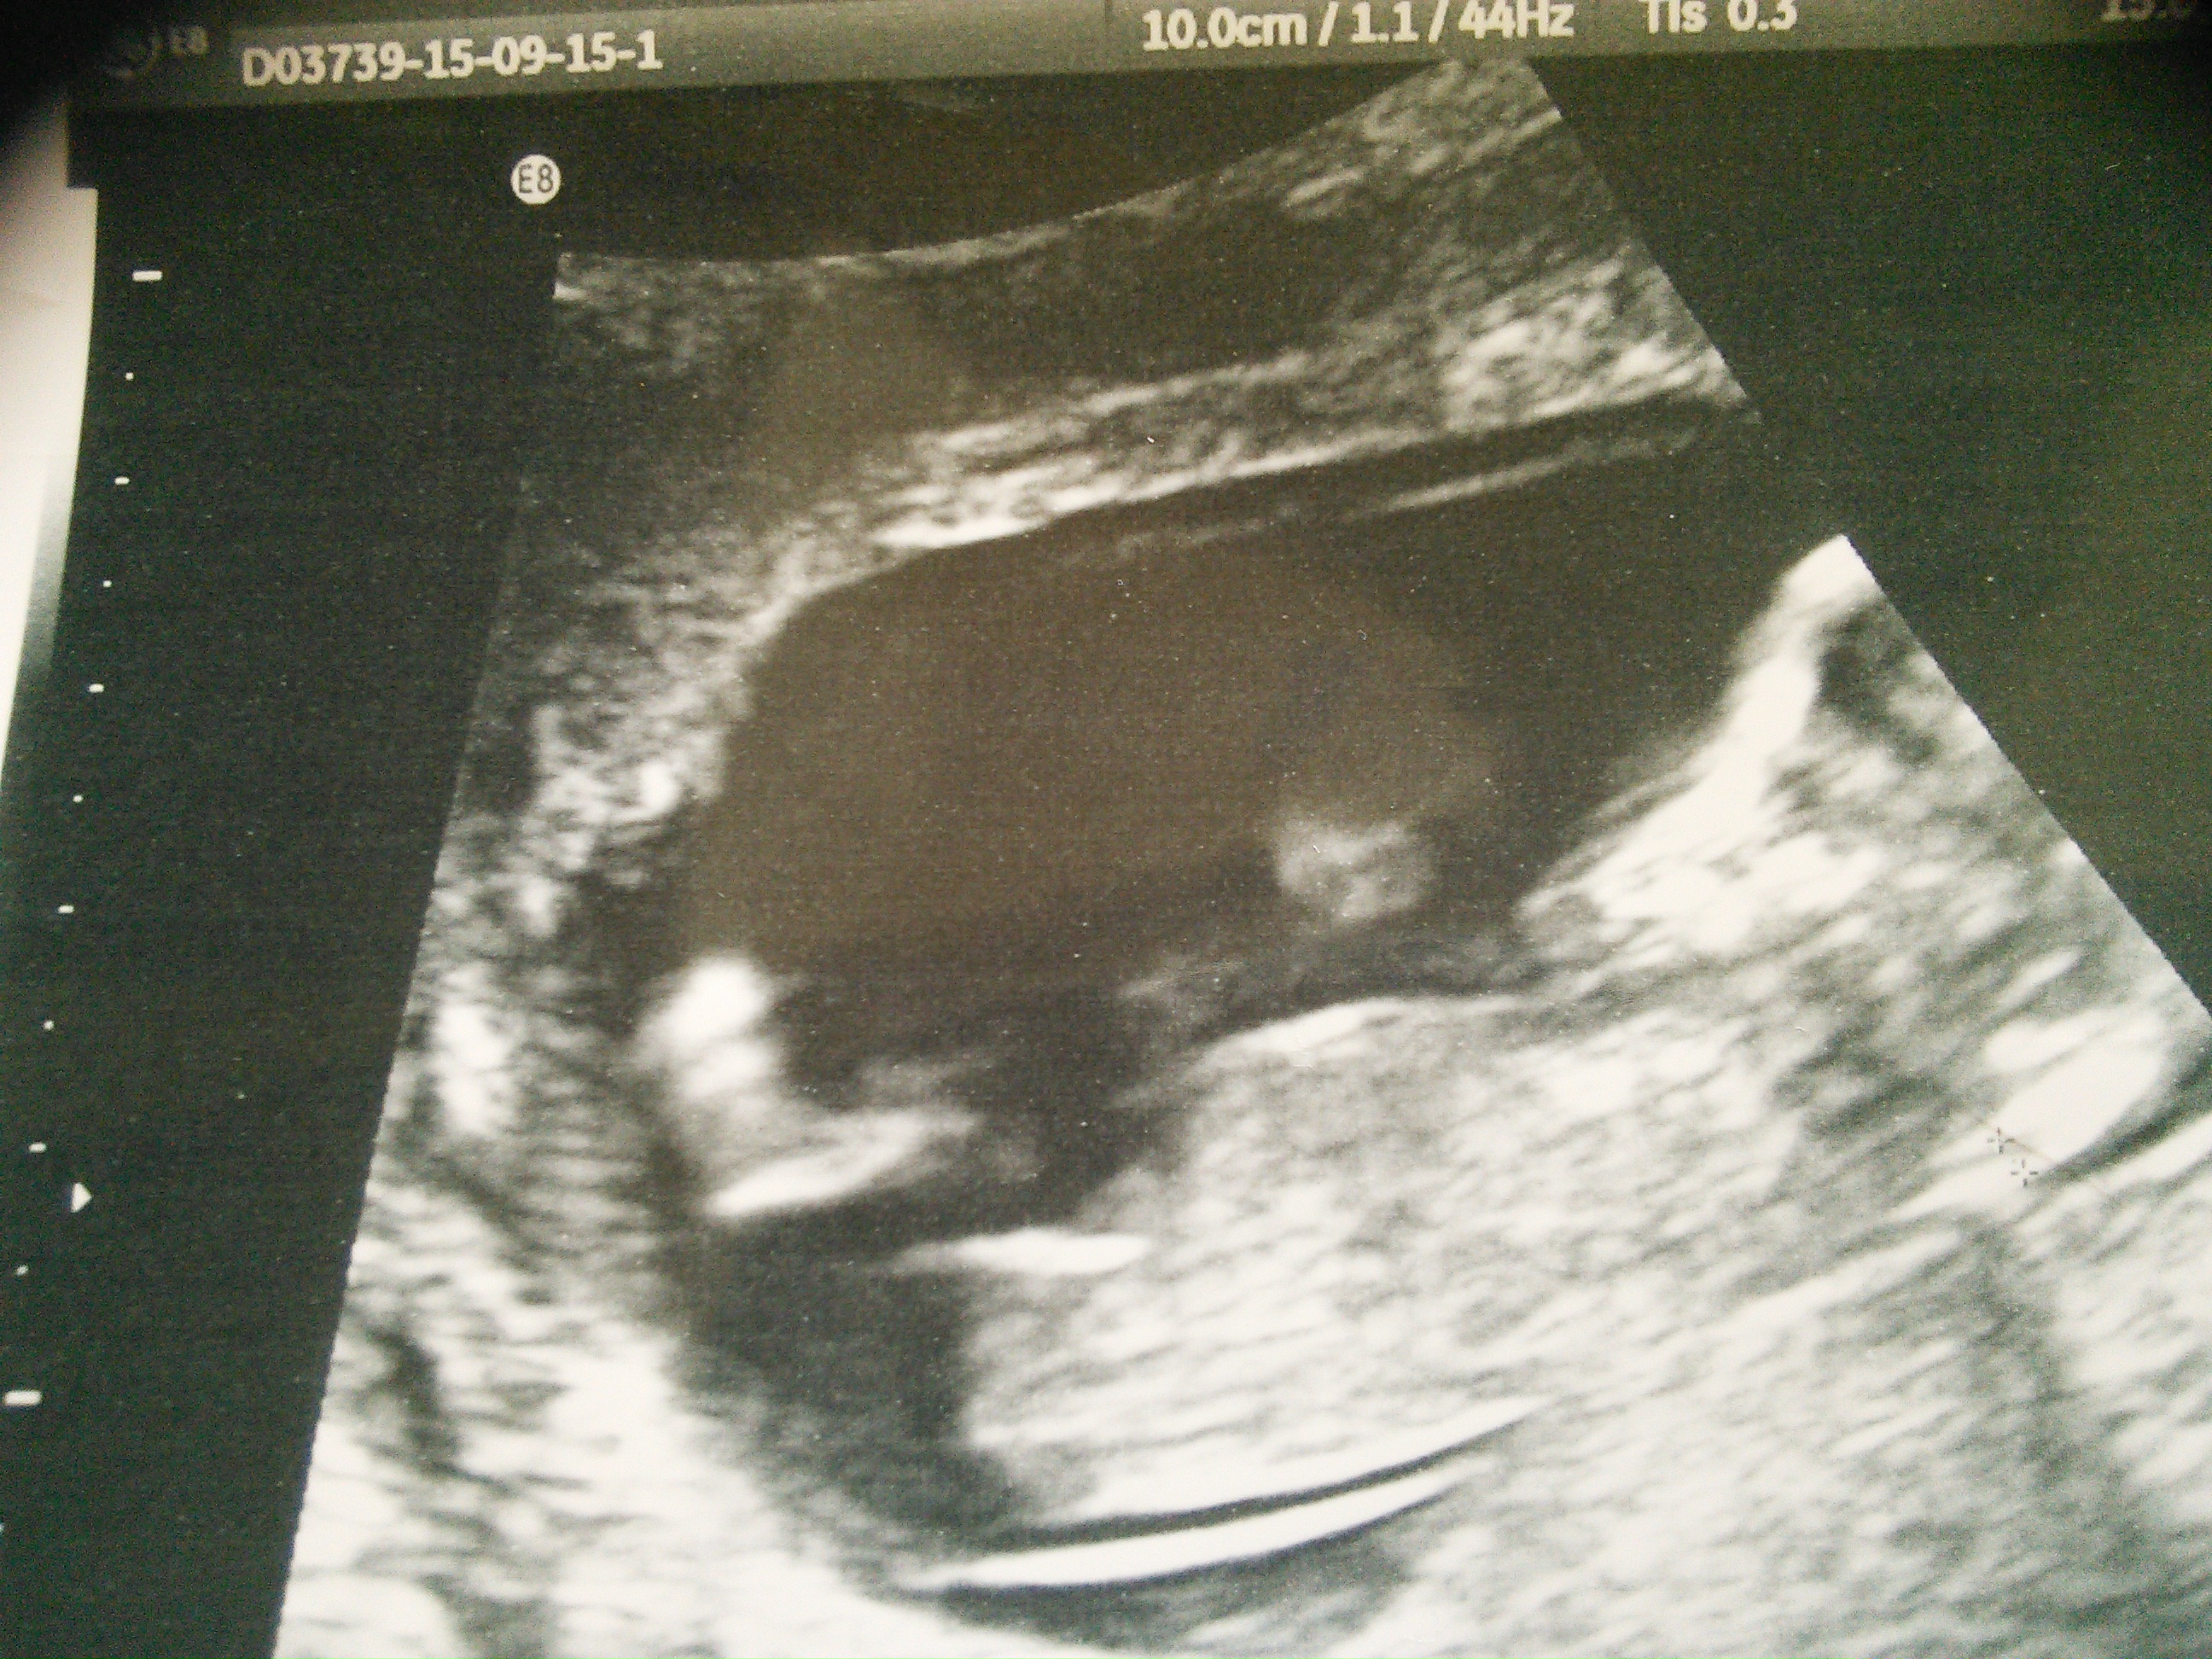

13 weeks 4 days - any clues gynae guessed maybe boy that he might have seen something - ughhhhh!

Is this the umbilical cord ?